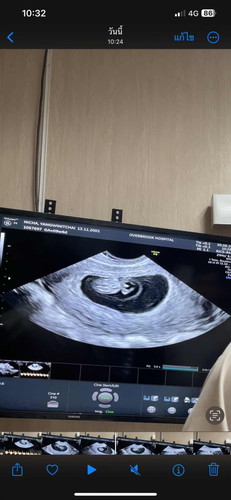

9วีค 6 วัน อัลตร้าซาวด์

ใครซาวเห็นเพศบ้างแล้วคะ ☺️ ทางนี้ต้องรอผลนีฟ อีกทีค่ะ เพื่อความแน่ใจ ❤️

ใช่ค่ะ ตอนนี้ 10วีค กับ 4 วันแล้วค่ะ ❤️

จู๋ชัดนะคะ

ใช่ค่ะ แต่ต้องรอผลนีฟอีกทีค่ะ คนโตเป็นลูกสาว ถ้าคนนี้ผู้ชาย สมใจพ่อมากค่ะ 🤭☺️